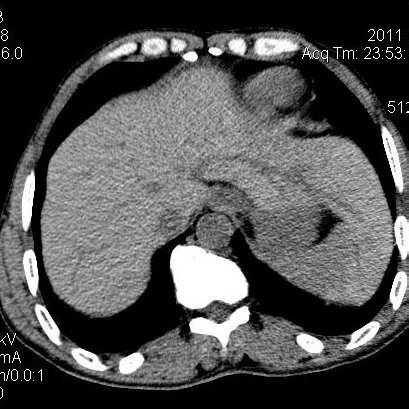

肝左叶发育异常

男性,55岁,骑摩托车摔倒后入院,自述右上腹疼痛

[backcolor=#FF0000]第一次诊断的时候也是这么肯定,可是床旁超声检查并没有发现明显异常,而且患者的一般症状都良好。还好临床只是保守治疗,没有立即手术,第二次复查的时候没有一点变化,又做了MRI检查,没有血肿,

这是一例肝左叶发育异常的,很个性吧~[/backcolor]